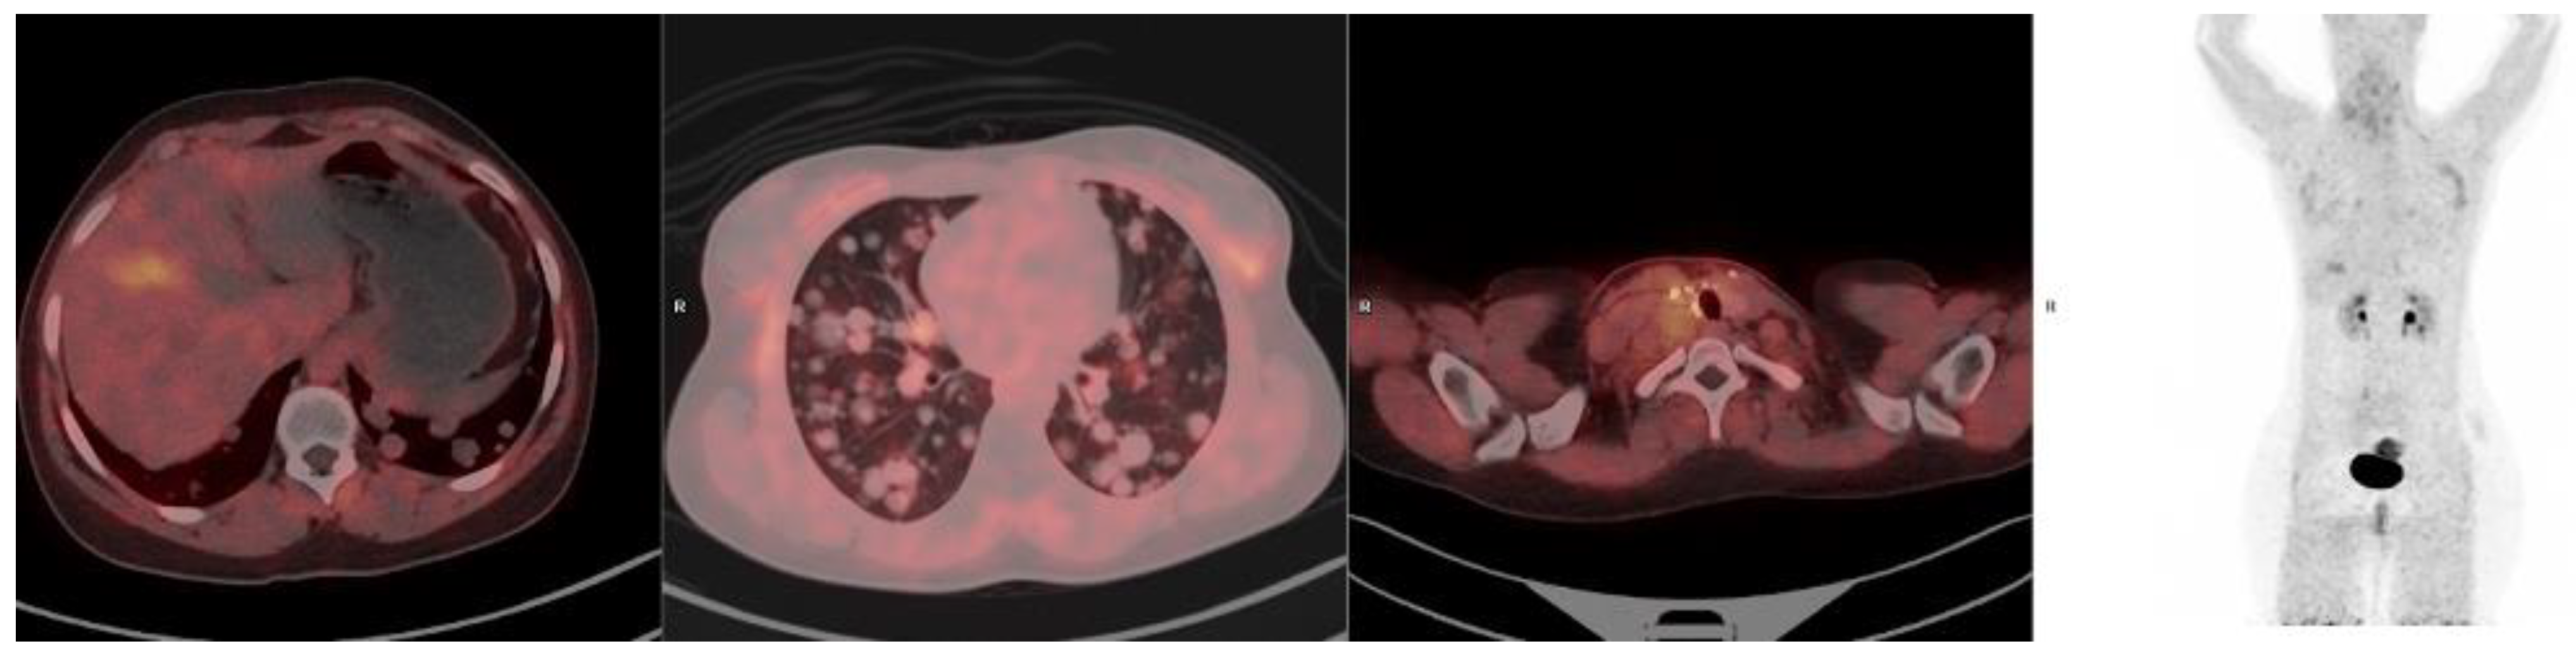

2. Fibroblast Activation Protein in Cancer Imaging

3. The Potential Role of FAPI PET Imaging in Specific Cancers

4. Summary of the Role of FAP-Based Imaging in Oncology